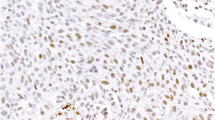

Immunohistochemical analyses, using the avidin-biotin complex method, were performed with primary antibodies directed against EGFR (clone 31G7; 1:25; Zymed Laboratories, San Francisco, CA, USA), HSP90 (anti-Hsp90; 1:70; Millipore, Billerica, MA, USA), MGMT (1:30; clone MT3.1, Thermo Scientific, Fremont, USA), the mismatch repair gene products MLH1 (1:100; clone G168-15; BD Transduction Laboratories), MSH2 (1:100; AB2; Oncogene Research, Cambridge, MA, USA), and MSH6 (1:200; clone 44; BD Transduction Laboratories), PMS2 (1.50; clone A16-4, BD Pharmingen, San Diego, CA, USA), L1CAM (1:100; L1-14.10; [25]), Her2/neu (polyclonal rabbit, 1:500; clone A0485; DAKO), DCC (1:100; G97-449; BD Pharmingen), and BRAF V600E (1:5; VE1; Spring Bioscience, Pleasanton, CA, USA). If necessary, antigen retrieval was achieved by microwave pretreatment in citrate buffer (HSP90, p53, MSH6) or by microwave pretreatment in 1 mM EDTA (MGMT, MLH1, MSH2). Immunohistochemical stains were considered as positive in few cells if less than 10 % of the tumor cells showed immunoreactivity, as focally positive if 10 to 70 % of the tumor cells showed immunoreactivity, and as positive if more than 70 % of the tumor cells showed immunoreactivity.

A total of 57 tumor tissues were available for additional molecular and immunohistochemical tests (Supplementary Tables 2 and 3), depending on the DNA quality and the size of the tumor samples. Fluorescence in situ hybridization (FISH) revealed amplification of c-MYC (up to ten signals per nucleus) in one case, low-level amplifications (between five and seven signals per nucleus) in 6 cases and a normal c-MYC copy number in 34 tumor samples. Immunohistochemical stains showed diffuse expression of DCC in non-neoplastic tissues. In contrast to this, 17 of 56 available tumors (30.4 %) showed complete loss of DCC expression, and 27 tumors (48.2 %) revealed significant reduction of DCC expression, displaying only very faint staining intensities. Only 12 tumors (21.4 %) showed regularly maintained DCC immunoreactivity, comparable to that in non-neoplastic tissues. Microsatellite instability was detected in 2 of 42 informative tumor tissues, revealing MSI in at least 2 of 3 markers. No tumor revealed MSI of only one marker. Aberrant expression of the mismatch repair gene products MLH1, MSH2, and MSH6 was not observed. In one of the microsatellite unstable tumors, MSH6 staining was considered not informative because of the complete absence of staining in tumor and control tissue. Additional PMS2 staining in the two microsatellite unstable tumors revealed lack of nuclear PMS2 expression in case 40, suggesting a PMS2 deficiency as cause of the MSI phenotype, and a reduction of PMS2 staining compared to surrounding non-tumorous cells in case 10. Mutational analyses of K-RAS comprising exons 1 and 2 revealed mutations in 2 of 41 tumor tissues tested (2 %), affecting codon 12 (GGT 12 GAT) and codon 13 (GGC 13 GAC) (Fig. 4). Membranous immunohistochemical expression of EGFR was observed in 19/45 tumors (42 %), with positive tumor cells ranging between 80 and 100 % in 14 cases, 40 % in 1 case, and 5 % in 4 cases. There were no EGFR mutations found in exon 18 (41 informative cases), exon 19 (n = 40), exon 20 (n = 31), and exon 21 (n = 26). Immunostaining with the BRAF mutation specific antibody V600E or with Her2/neu was negative in 42 tumors. Loss of nuclear MGMT expression was lost in 13/51 tumors (26 %) (Fig. 5). High immunohistochemical expression of L1CAM was recognized in 39/54 tumors (72 %), with diffuse staining in 29 cases and focal staining in 10 cases. Finally, cytoplasmic HSP90 expression was observed in 47/48 cases (98 %). Seven cases, including one cytoplasmic-negative tumor, showed nuclear HSP90 immunoreactivity. There were no significant differences between PACs and MACNECs. None of the above molecular findings correlated with the cytogenetic clusters.

Molecular and immunohistochemical characteristics of PACs: a FISH analysis showing c-MYC amplifications; b immunohistochemical loss of DCC expression in liver metastasis (regular DCC expression in adjacent liver tissue, depicting red); c PAC (case 40) with loss of PMS2 expression in tumor cells, while intratumoral lymphocytes show regular nuclear PMS2 positivity (depicting red); d, e k-ras mutations in two cases (indicated by arrows)